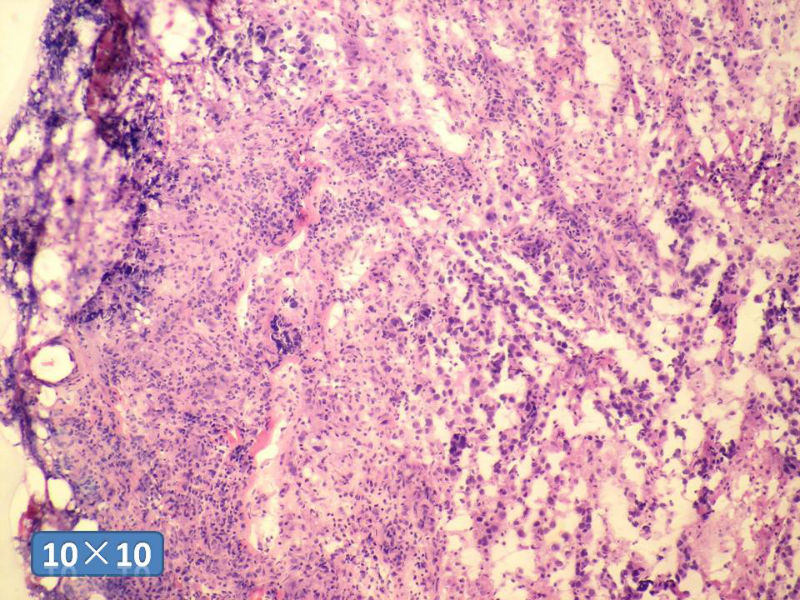

女性,50岁,乳腺肿物,冰冻切片(图1-25)